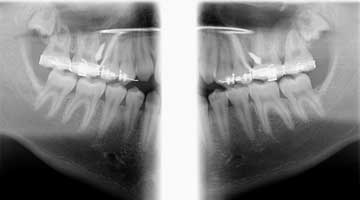

In the case of anterior open bites, TADs are placed bilaterally on the buccal aspect of the maxilla between the second premolar and first molar. The greatest amount of interradicular bone in the posterior maxilla is found in this region, about 5–8 mm from the alveolar crest (3). In the case of less-than-ideal interradicular bone, the TAD could be placed palatally or roots can be diverged before TAD placement (3). The maxillary molars and premolars are banded and bracketed respectively and ligated with bilateral, segmented stainless steel wires. Once levelling and aligning of these teeth are complete, the TAD is placed and a nickel titanium coil and elastic chain are used to connect the TAD to the mesial of the first premolar and hook of the second molar band. This creates a light and continuous force to produce intrusion en masse of the first premolar to the second molar bilaterally.

In conjunction with TAD placement, a TPA (transpalatal appliance) is placed to prevent the intruding molars and premolars from tipping buccally (3). An acrylic button is placed on the center of the TPA and the patient is instructed to press occasionally on the button with the tongue. Tongue pressure on the TPA also aids in tooth intrusion (3).

Case report

A healthy 15-year-old male presents to the clinic with an anterior open bite. His case is outlined in the figures below.